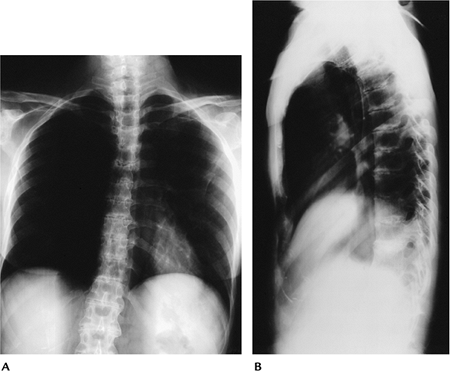

![]() |

FIGURE 13-32 Ochronosis. AP (A) and lateral (B) radiographs of the thoracic spine showing diffuse disc space narrowing and disc calcification.